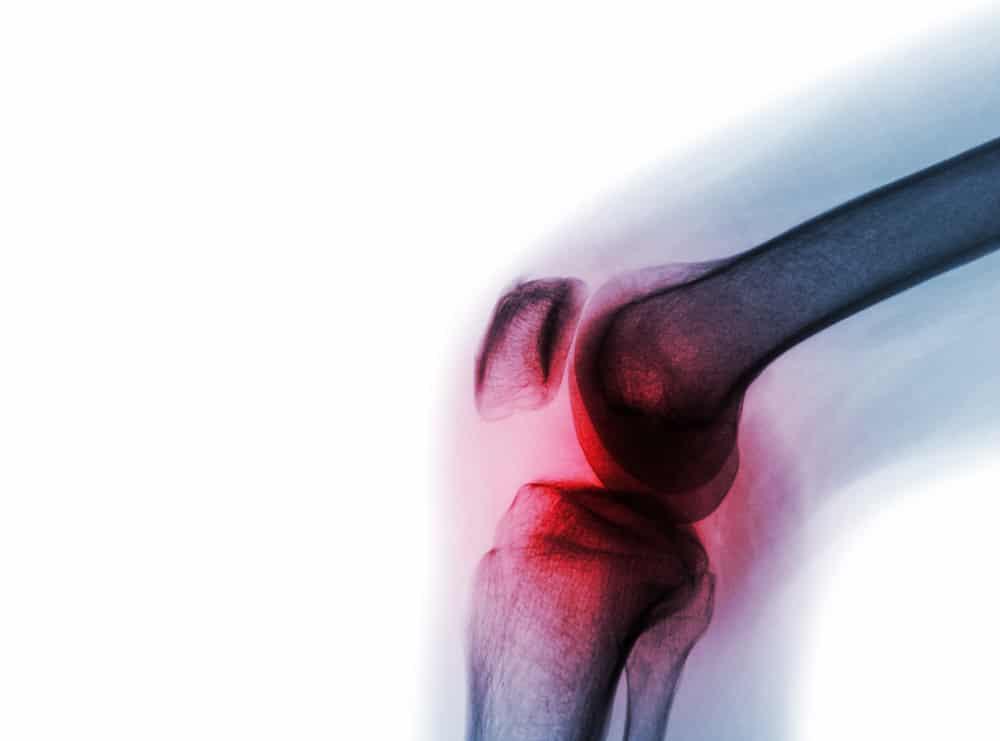

- ဓာတ်မှန်ရိုက်တာတွေ လုပ်ရမှာပါ။